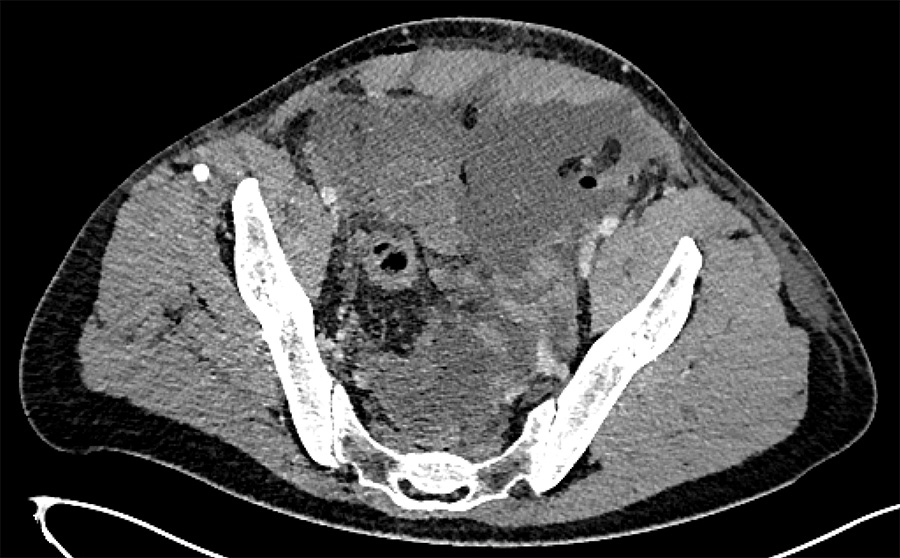

The surgery was performed as planned, but on day 4 after surgery, the patient started experiencing abdominal pain, nausea, and vomiting. At abdominal palpation, we found a boardlike abdominal wall in the left lower quadrant. The abdominal contrast-enhanced CT scan revealed a left retroperitoneal collection with intraperitoneal extension, interpreted as a hematoma that was compressing the ileum, and the urinary upper tract, responsible for moderate bilateral hydronephrosis (Fig. 1).